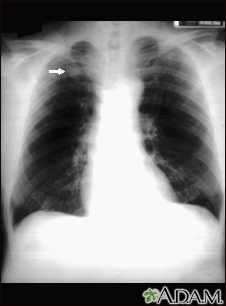

Pulmonary nodule - front view chest x-ray